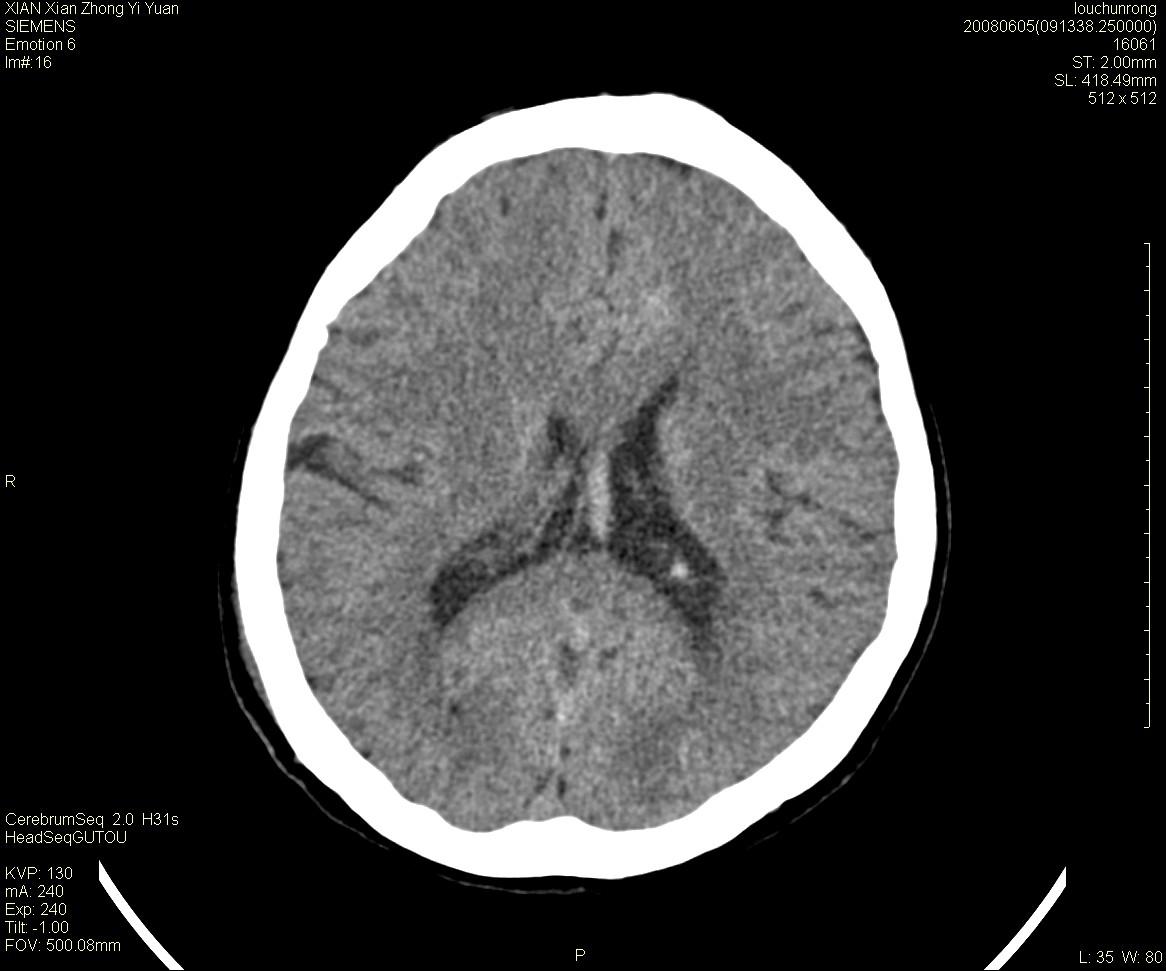

标题: CT13860:F52Y,,头外伤致头晕半天,以前无不适。 [打印本页]

标题: CT13860:F52Y,,头外伤致头晕半天,以前无不适。

层厚2mm。

左侧侧室内血管异常增粗,考虑血管变异或血管瘤可能,余未见异常

静脉窦血栓? mri检查

大家看左额叶大脑镰旁高密度影

两侧脑室体部距离增宽,胼胝体发育不良?

中线附近、枕叶近枕骨处及脑内多发点条状强化影,考虑血管异常?

大脑大静脉池内的密度不均,双侧脑室增宽,我看右异常这块。战友们看看

侧脑室前角变形、变窄,考虑侧脑室粘合;余未见明显异常。